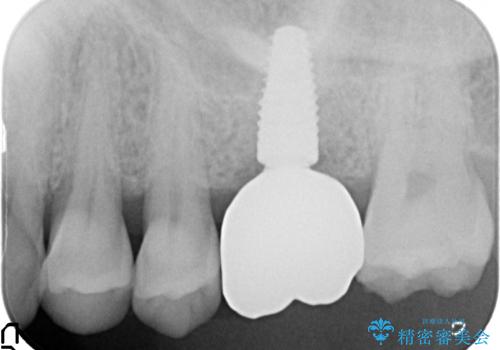

- 44万円(インプラント・チタンカスタムアバットメント・ジルコニアクラウン・仮歯)費用は治療当時の料金となります

歯が割れるほどの咬合力が強い方でしたので、3本の歯を2本で支えるブリッジではなく、咬合負担能力の増えるインプラント治療にメリットが大きいと言えます。